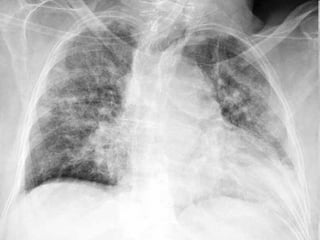

57 Pneumococcal pneumoniaPneumococcal pneumonia Rupper lobe consolidation with Air BronchogramR upper lobe consolidation with Air Bronchogram